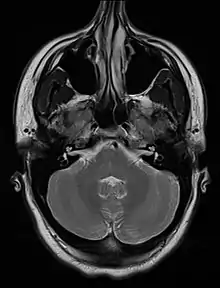

| An MRI image showing a congenitally deviated nasal septum, bowed to the left between the eye sockets | |